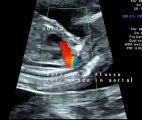

Cuore sinistro ipoplasico